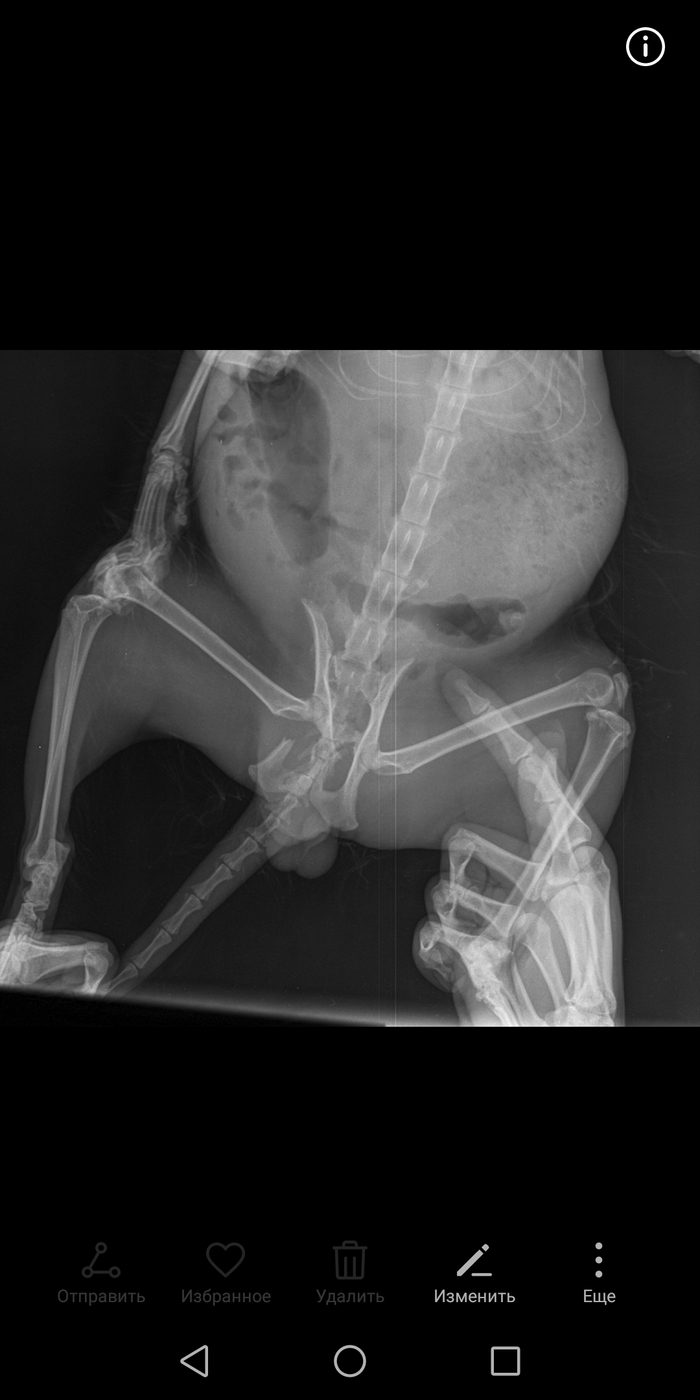

Приветствую, Пикабу. Котик Марк восстанавливается после сложной операции.

У котика был сломан таз. И поэтому его бросили. Голодный, в 0ололе не коль дней сидел в ЖК. Пока не вылез к людям.